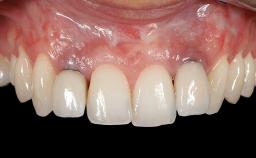

GBR and Soft-Tissue Augmentation Following Explantation to Rehabilitate a Soft- and Hard-Tissue Defect

It is sometimes necessary to remove and replace compromised implants. This case is a clear example of the need for multiple steps to achieve an optimal therapeutic result for patients with non-salvageable implants. It illustrates how the lost soft and hard tissues were rebuilt in a sequence that improved the healing of the hard tissues and assured their long-term stability. The 35-year-old healthy patient presented with clinical attachment loss on the proximal and lingual surfaces of the natural dentition. Some gingival recession was present on natural teeth, particularly in the posterior sextants (S1, S3, S4, and S6).

Soft Tissue Grafting Staged

Prosthesis Type FDP